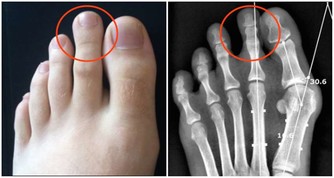

第八名:海鮮就啤酒很多人喜歡就海鮮喝啤酒,不過如果邊吃海鮮邊喝啤酒,這種吃法也會傷及腎臟。

海鮮產品是高蛋白食物,含有嘌呤和苷酸成分,和啤酒混合在一起,會產生過多的尿酸和尿素氮等代謝物,

加重腎臟負擔,易導致高尿酸血症,甚至腎結石、尿毒癥。